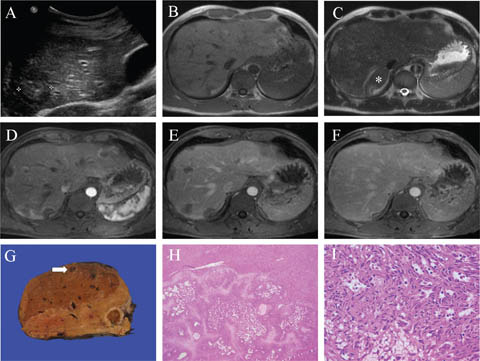

Fig 4

Figure 4. Representative images of intrahepatic cholangiocarcinoma. A and B. The lesion shows low signal on the T1 weighted image (A) and intermediate to high signal on the T2 weighted image (B) with surrounding mild peripheral intrahepatic biliary dilatation. C. The lesion shows intense diffusion restriction on the b=150 s/mm2 image. D, E, and F. Following gadolinium administration, the lesion shows heterogeneous arterial (D) and portal phase (E) enhancement (predominantly in the periphery), with progressive centripetal filling-in, completely hyperenhancing on the delayed phase (F) at 5 minutes. G. A partial hepatectomy from a separate patient shows a tan-white sclerosing lesion grossly, with extensive involvement of a probed large duct. H. Microscopically an invasive adenocarcinoma (white arrow) is seen arising from a large duct (black arrow). I. Well-formed glands are seen invading a nerve. Slides are stained with Hematoxylin and Eosin. Total image magnification: H - 25X; I - 200X.

Grossly, large duct ICCAs often present as mass lesions around the larger caliber bile duct branches with invasion into the surrounding hepatic parenchyma. Some large duct ICCAs will not form a mass lesion but rather spread along bile ducts in a diffuse and longitudinal manner (referred to as a “periductal infiltrating” pattern of growth) (42). They may be found in association with macroscopically visible intraductal papillary neoplasms of the bile ducts, not discussed within this chapter. Small duct ICCAs typically present as a peripheral mass-forming lesion that is white-grey and nodular, often within a background of cirrhosis (62% of cases) (40).

Microscopically, large duct ICCAs are invasive adenocarcinomas of tubular or solid growth patterns with extensive desmoplastic reaction, sclerosis of larger bile ducts, portal tract involvement, frequent perineural and lymphatic space invasion, and frequent lymph node metastasis. They may be found in association with microscopically visible biliary intraepithelial neoplasms, which are not discussed in this chapter. Small duct ICCAs show variable proportions of slit-like lumens in cord-like growth patterns, or distinct lumens in tubular growth patterns found replacing the hepatocytes in regenerative nodules. All ICCAs have small-to-medium-sized cuboidal or columnar cells, eosinophilic or vacuolated cytoplasm, small nuclei, and variably prominent nucleoli. The diagnosis of adenocarcinoma is typically readily made by morphology alone; however, poorly differentiated cases may lack apparent glandular differentiation and require IHC to exclude other primary neoplasms (for example, poorly differentiated HCC). Combined hepatocellular cholangiocarcinoma is a rare malignancy composed of both unequivocal HCC and ICCA components within the same tumor and may occasionally be encountered in biopsy specimens. ICCA does not show a specific morphology or IHC profile. Therefore, careful clinical and radiological correlation is essential to rule out a metastatic adenocarcinoma from another site.

On imaging, the mass-forming pattern of ICCA demonstrates a well-circumscribed, often large, lobulated mass frequently with satellite nodules. The periductal-infiltrating pattern demonstrates growth along bile ducts with an elongated, branching, spiculated appearance. Capsular retraction, more typical of the mass-forming pattern, is characteristic but not pathognomonic for ICCA. Upstream biliary ductal dilatation is typical but not specific.

Mass-forming ICCAs are typically hyperechoic on ultrasound if larger than 3 cm and isoechoic or hypoechoic if smaller (43). A peripheral hypoechoic rim is seen in approximately 35% of cases (43). On unenhanced CT, they are typically hypoattenuating (43), and calcification may be present. They are typically heterogeneously T1WI hypointense and demonstrate a T2WI hyperintense peripheral rim with central hypodensity, which may be hyperintense in the setting of internal necrosis (43). The enhancement pattern on MRI and CT is typically arterial phase continuous rim-like enhancement (targetoid) with progressive, concentric centripetal fill-in on the portal-venous phase and persistent enhancement on delayed imaging (43).